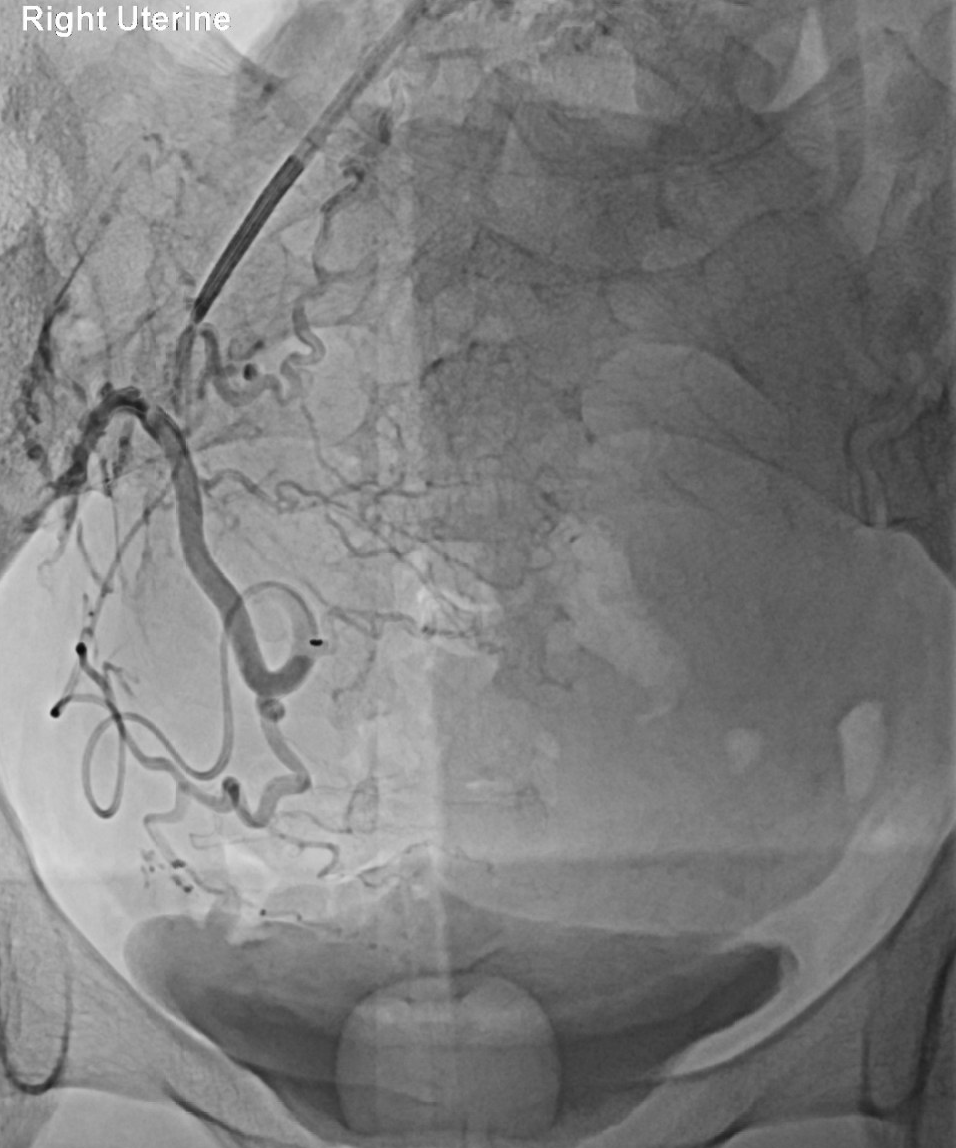

Using X-ray guidance, the catheter is guided to the uterine arteries

Tiny particles are injected to block blood flow to the fibroids